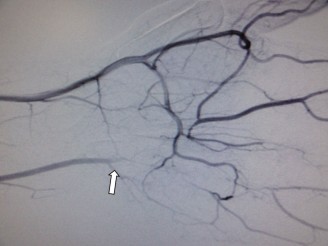

The vascular supply to the scaphoid is the single most critical anatomical factor dictating fracture healing. The primary arterial supply is derived from the radial artery. As the radial artery traverses the anatomic snuff box, it gives off dorsal carpal branches that enter the scaphoid through the dorsal ridge, supplying the proximal 70% to 80% of the bone via a retrograde intraosseous network. A secondary, minor volar vascular contribution enters the distal pole via branches from the superficial palmar arch.

Because the blood supply to the proximal pole is entirely dependent on retrograde flow from the distal intraosseous vessels, fractures occurring at the waist or proximal third of the scaphoid abruptly sever this vascular tether. Consequently, proximal pole fractures carry an exceptionally high risk of avascular necrosis (approaching 100% in very proximal lesions) and non-union, necessitating aggressive surgical management and often vascularized bone grafting.

Scaphoid non-union occurs in approximately 5% to 10% of treated fractures, but this rate skyrockets to over 50% in displaced or proximal pole fractures. AVN of the proximal pole complicates up to 30% of waist fractures and nearly 100% of proximal fifth fractures. When non-union occurs with a viable proximal pole, revision ORIF with non-vascularized structural bone grafting (e.g., iliac crest) is indicated. However, if the proximal pole is necrotic (as evidenced by lack of punctate bleeding intraoperatively or absent enhancement on MRI), a vascularized bone graft is mandatory. The 1,2-Intercompartmental Supraretinacular Artery (1,2-ICSRA) graft, pedicled from the distal radius, or a free medial femoral condyle vascularized graft are the procedures of choice.